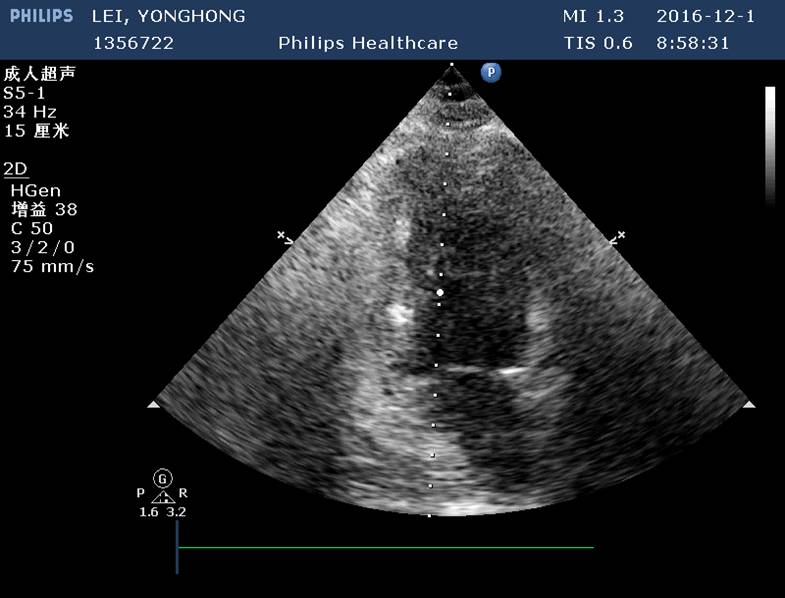

心动超声

左室壁节段性运动异常(室间隔心尖段、心尖部、前壁心尖段);

左室整体收缩功能正常(较前明显改善),EF62%